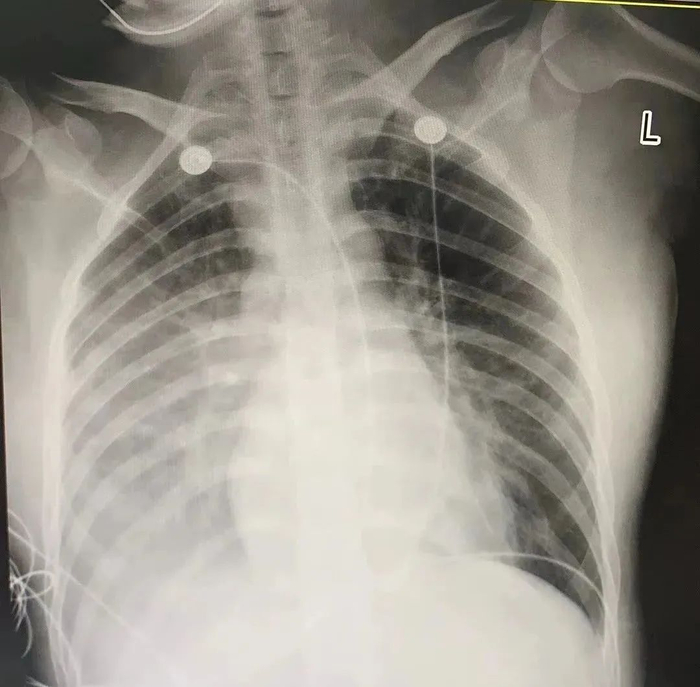

给燕琼照了胸片后,郁树亮邀请了专家会诊。当时,深圳市人民医院ICU主任刘雪燕、深圳市第二人民医院ICU主任孟新科、血液科主任杜新都还在生病,于是决定视频会诊,讨论燕琼的情况。

胸片显示,燕琼右肺有大量阴影,典型的肺炎。

另外,病毒也侵犯了她的心肌。检查显示,她的心肌酶显著升高。

在相关医护的共同努力下,后续复查胸片显示:肺部炎症已完全吸收,心肌酶已完全正常。